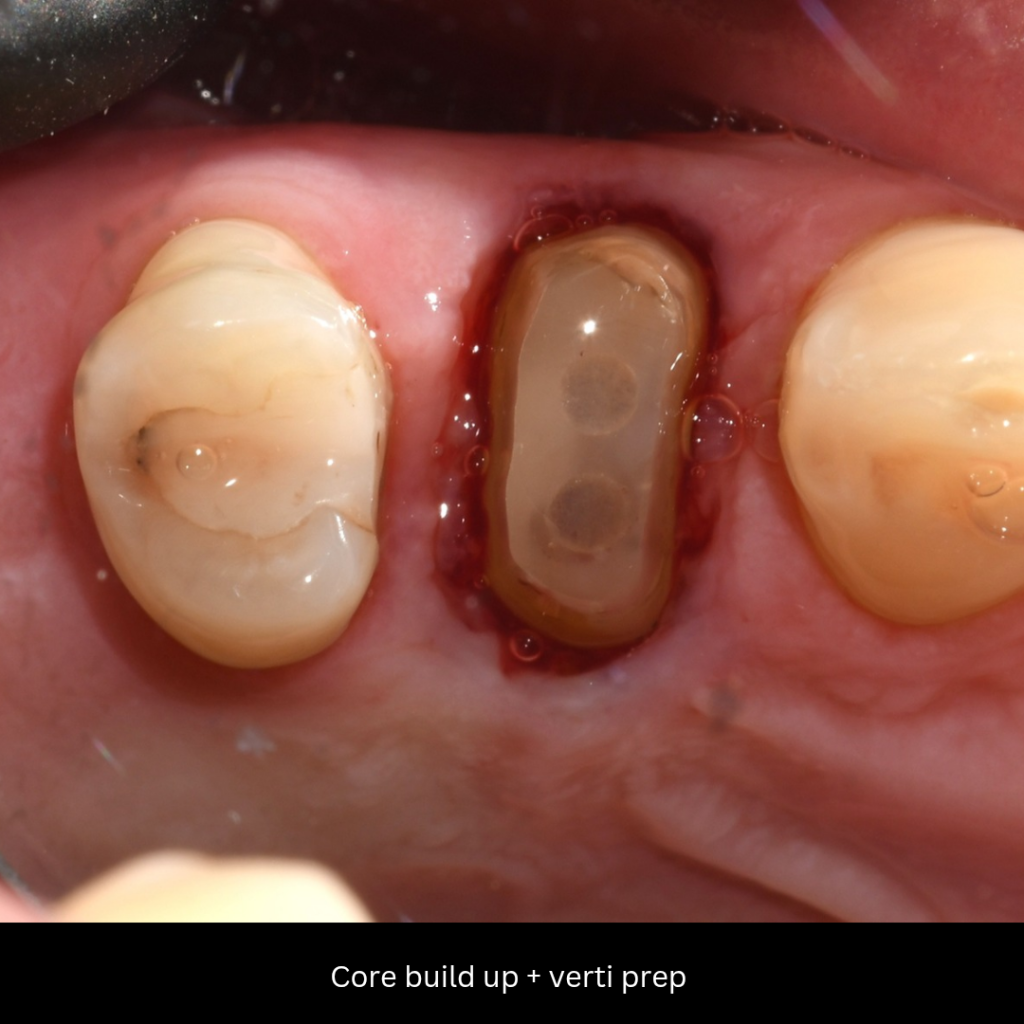

Phase II: Core Build-up and Vertical Preparation (BOPT)

4. Post-Space and Core Foundation

Fiber Post Cementation: After preparing the post space, a Fiber Post was cemented using a dual-cure adhesive cement.

Core Build-up: The coronal foundation was built using EverX flow Core to establish initial coronal integrity.

5. Vertical Preparation and Biological Width Management

Ferrul Management: Due to the absence of a substantial ferrule, the case necessitated a Vertical Preparation utilizing the Biologically Oriented Preparation Technique (BOPT) philosophy.

-

Preparation: The tooth was prepared vertically using specialized diamond burs (specify type/head if possible) to create a knife-edge/edgeless preparation, extending slightly into the sulcus.

Osteotomy : To ensure proper biological width and tissue health, a Closed Ostectomy (minor osteotomy) was performed at the time of preparation to establish a stable and healthy sulcus depth for future margin placement.

fiber post with ever x core